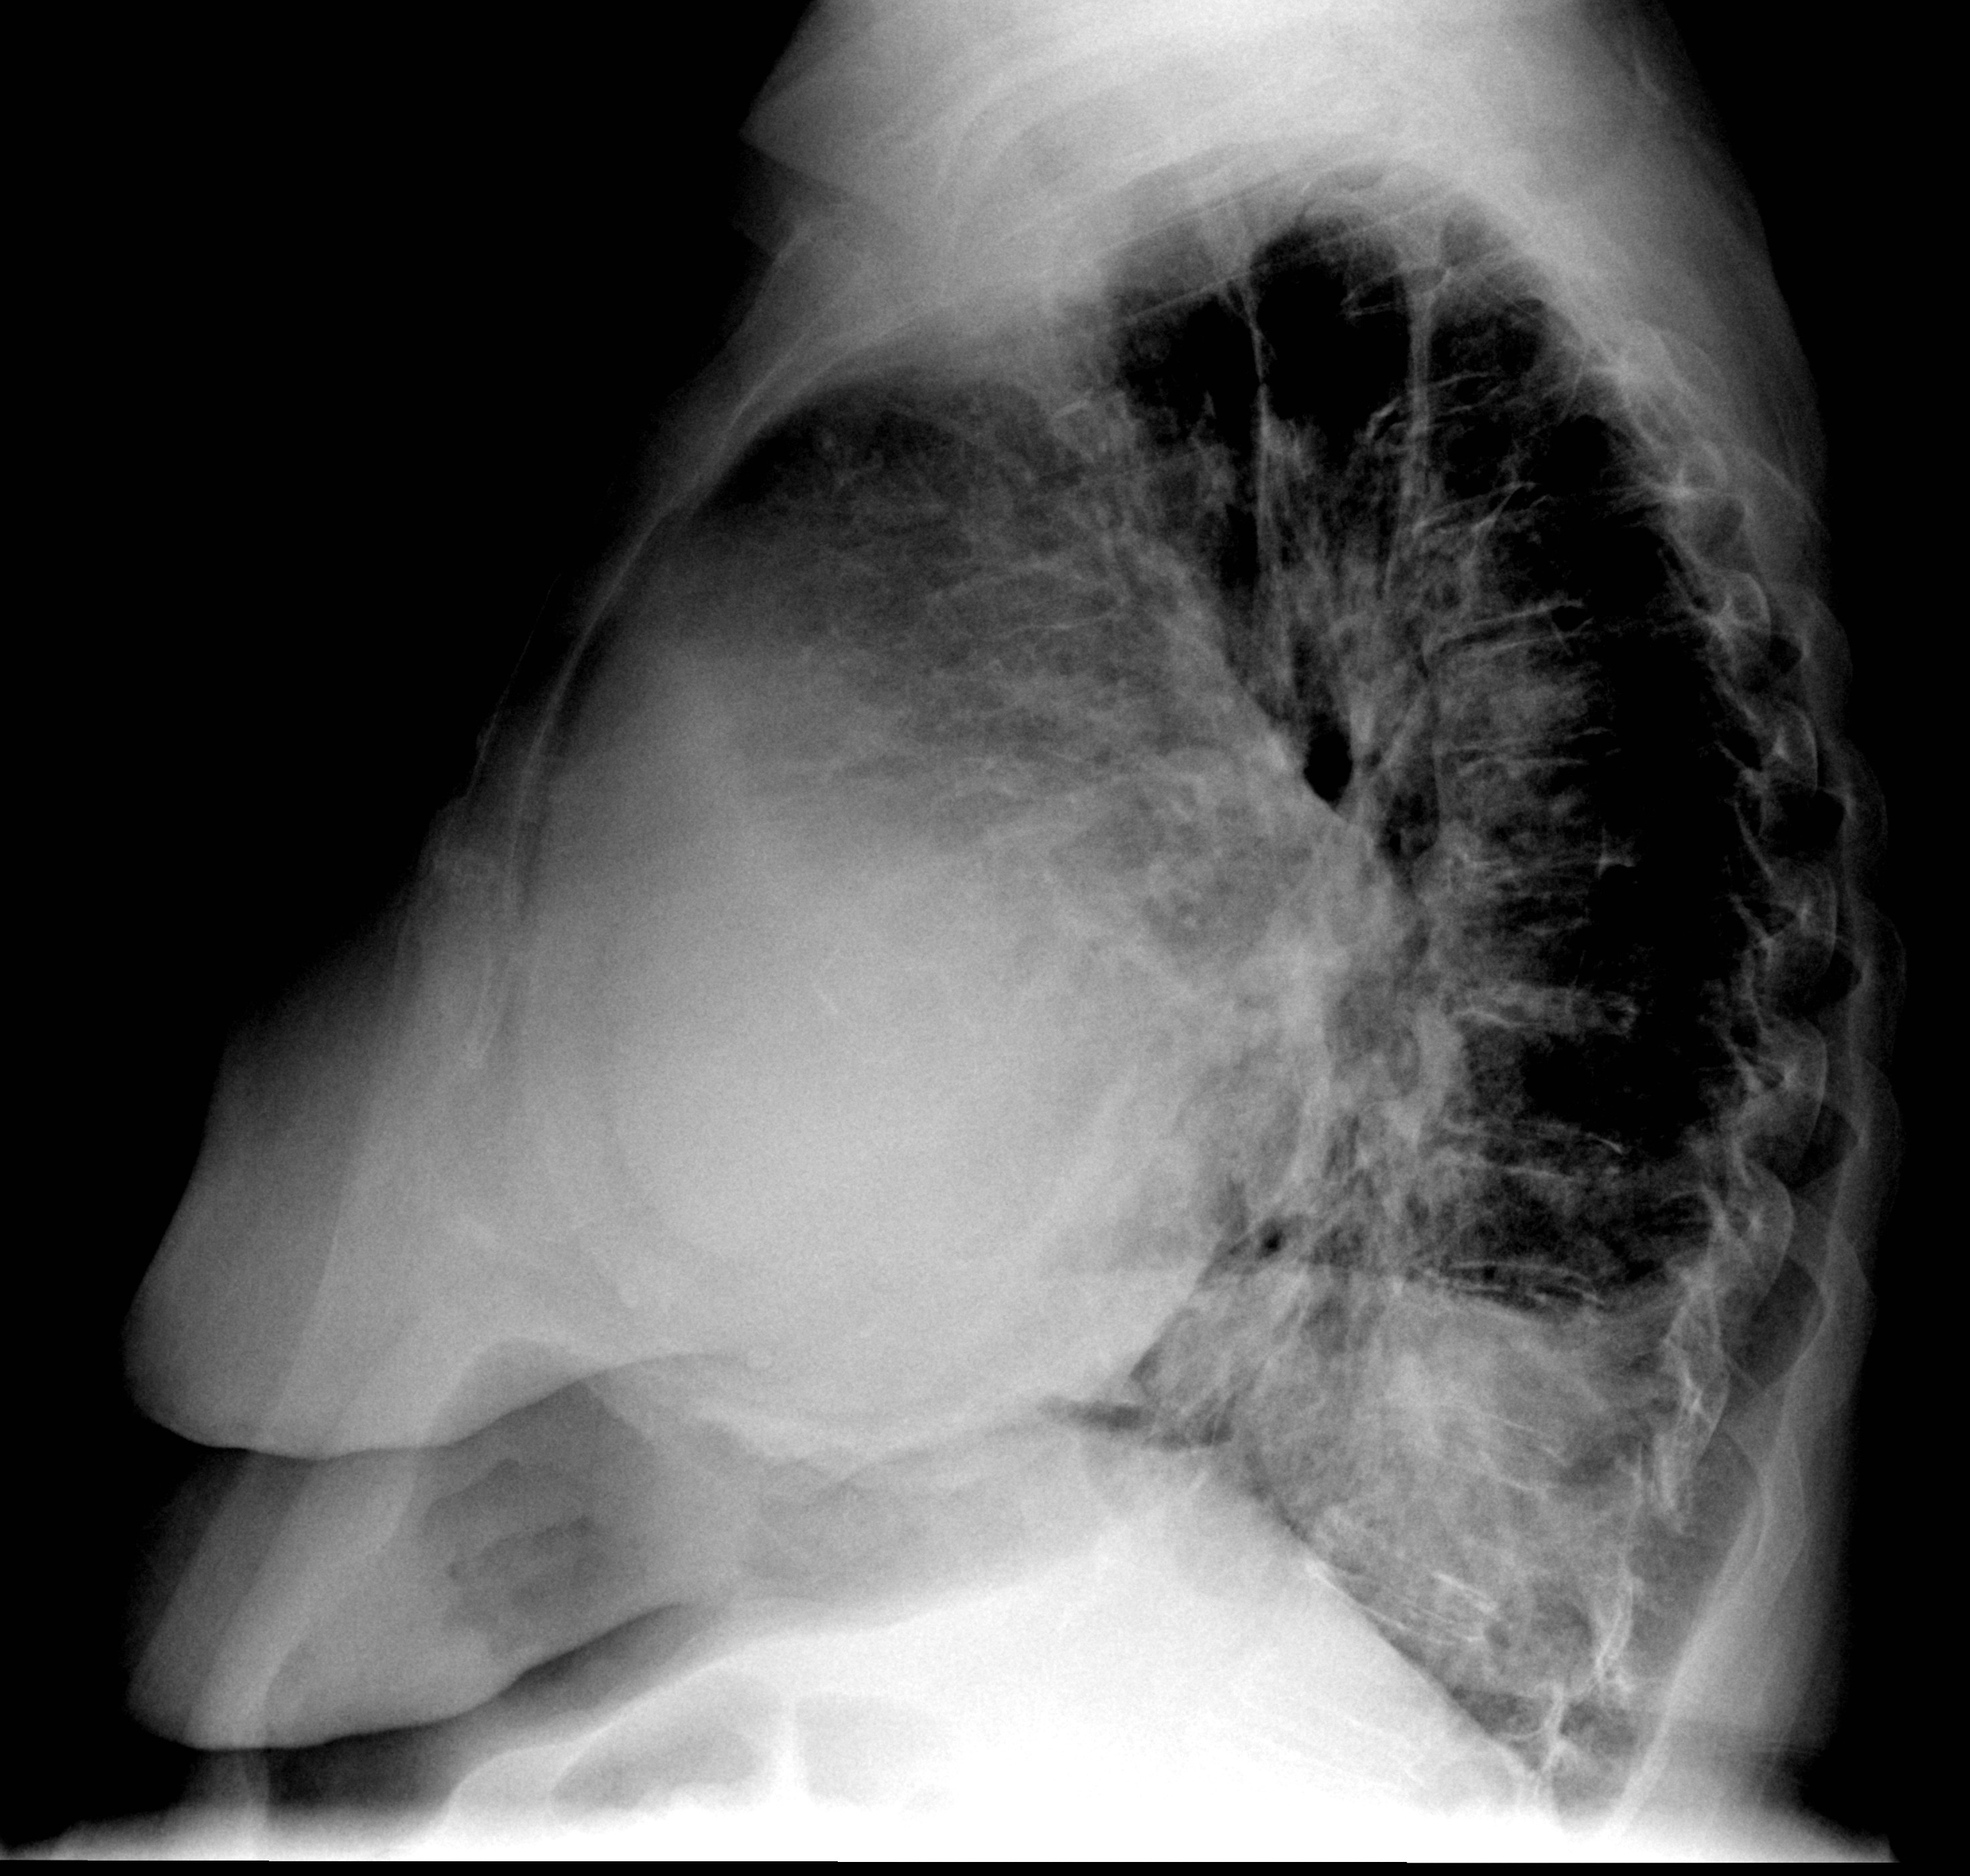

Case 7b Peric effusion

Case 7b

Peric effusion